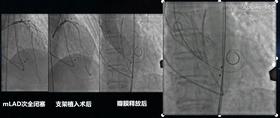

左:mLAD次全闭塞;中:支架植入术后;右:瓣膜释放后

阵发性房颤合并冠心病反复支架内再狭窄患者一站式融合手术